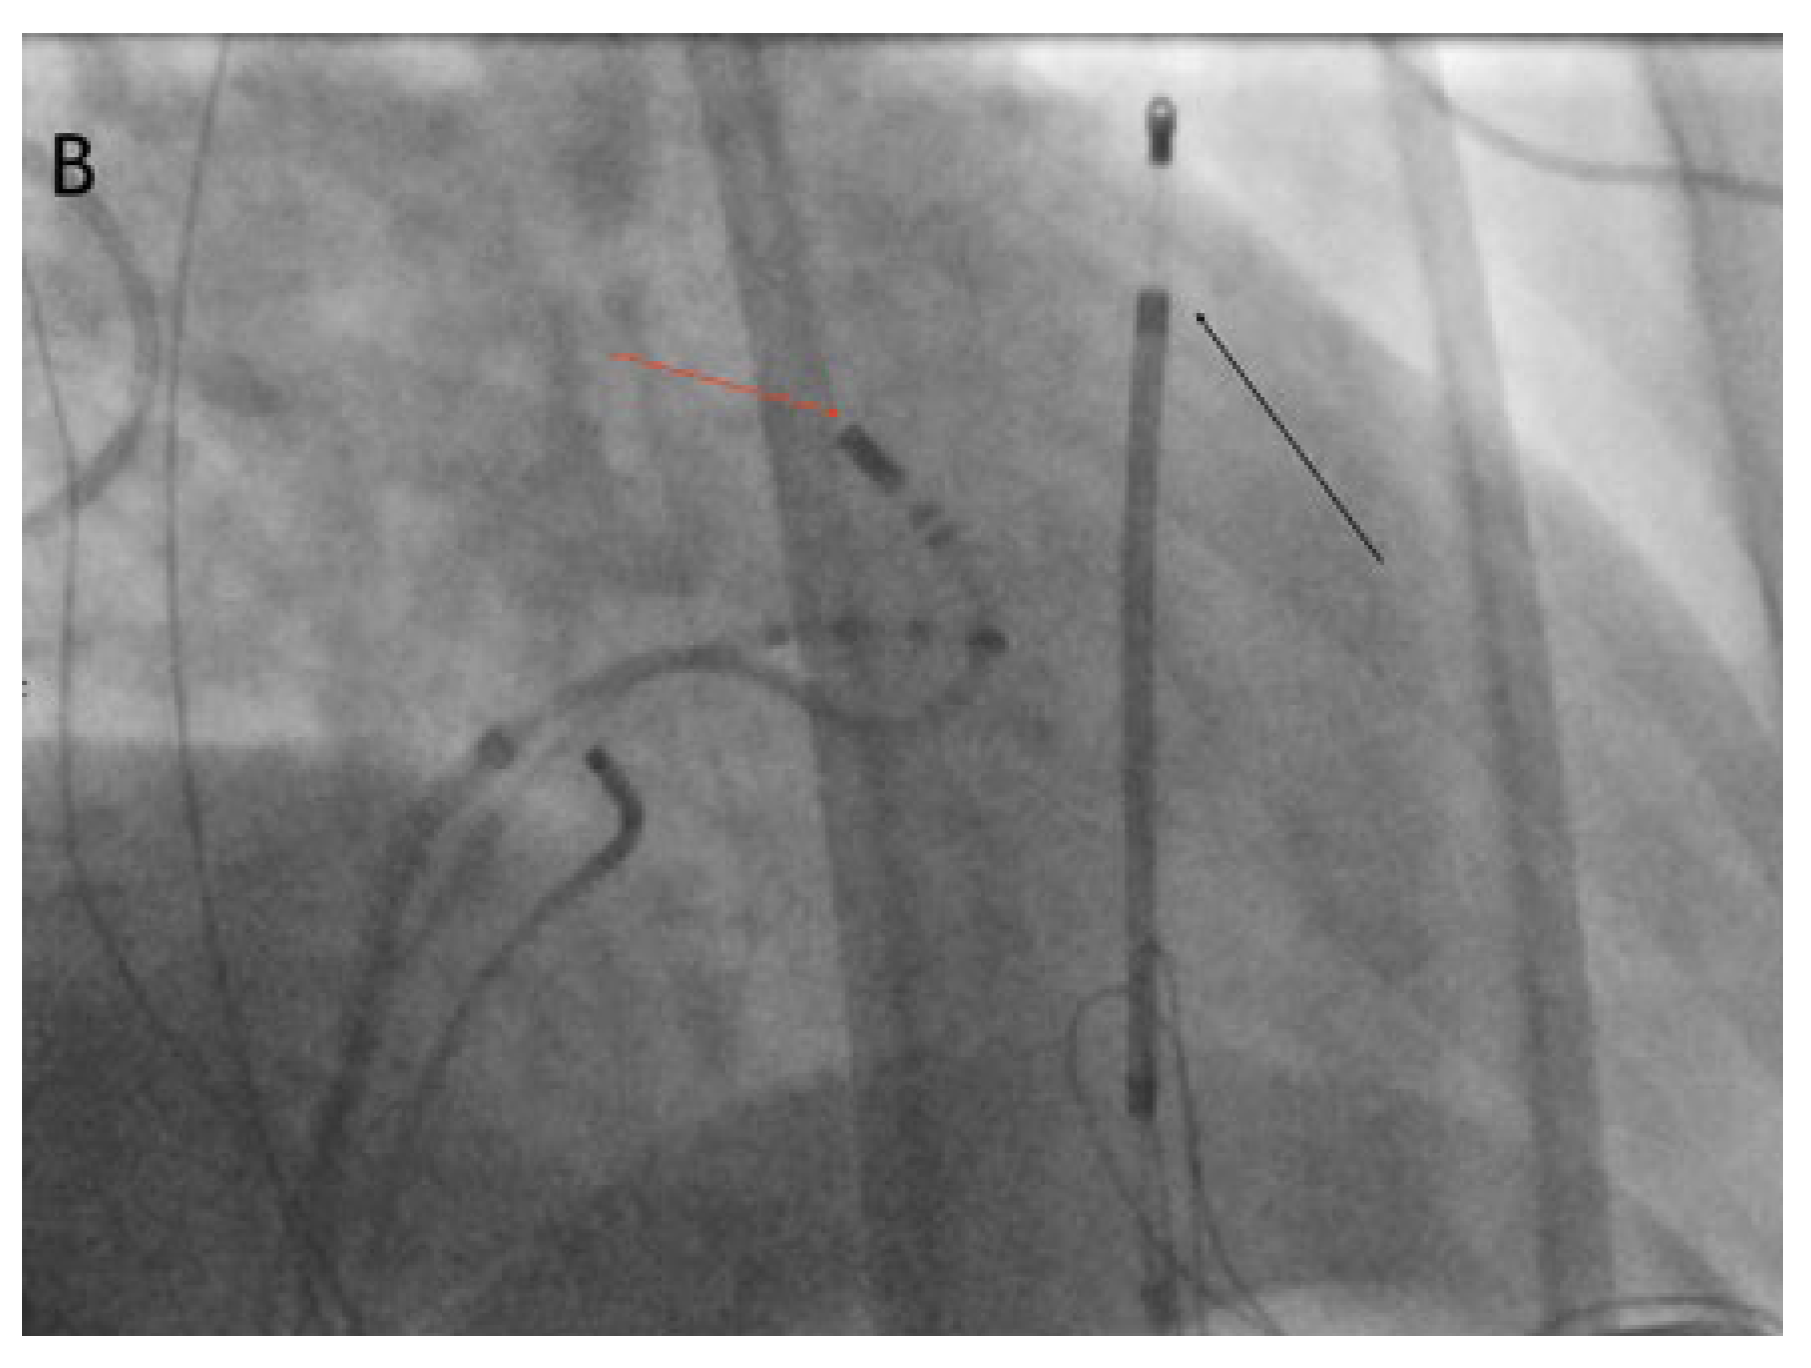

Clinical case